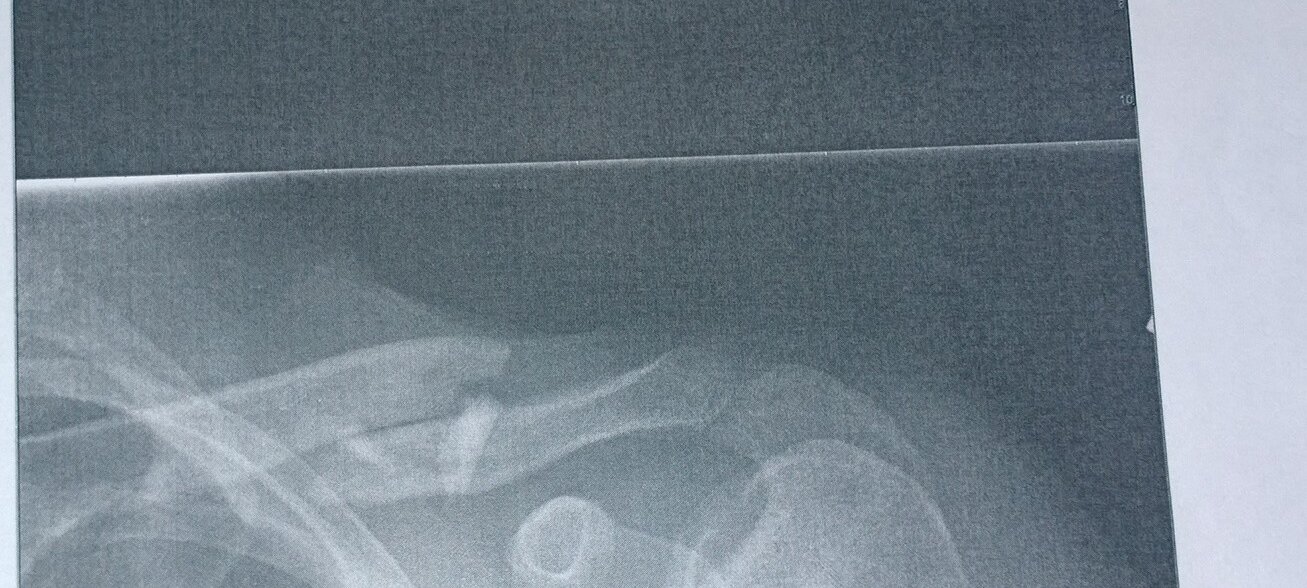

tPq9yYlUyXGyWM3WcvY8MdpsKyGiDRoY7Ace84Je4ZWelcome_to_a_comet2234dma-66dma-226WP_20141114_001WP_20141114_002WP_20141114_003WP_20141114_004WP_20141114_005OUCH!! It's Broken

2014-11-14 11/14-15/14